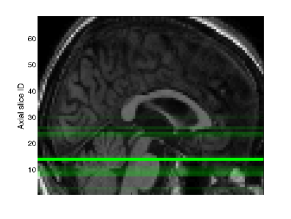

In summary, we consider a global view of data and a single GP which is specified with multiple covariance functions and aimed at single task learning. Despite the global view, the subtlety of MKL-AsRD should be noted. We wish to exploit the locality information in order to better capture the spatial patterns of brain atrophy. In this regard, we consider the portions of high-dimensional inputs, instead of the clusters obtained by an analysis of the joint feature space (Figure 1).

X= x1,1 x1,2 x1,3 x1,d x1,D xk,1 xk,2 xk,3 xk,d xk,D xN,1 xN,2 xN,3 xN,d xN,D []local viewglobal viewsubspace𝑋 subscript𝑥11 subscript𝑥12 subscript𝑥13 subscript𝑥1𝑑 subscript𝑥1𝐷 subscript𝑥𝑘1 subscript𝑥𝑘2 subscript𝑥𝑘3 subscript𝑥𝑘𝑑 subscript𝑥𝑘𝐷 subscript𝑥𝑁1 subscript𝑥𝑁2 subscript𝑥𝑁3 subscript𝑥𝑁𝑑 subscript𝑥𝑁𝐷 fragments[fragments]local viewglobal viewsubspaceX=\leavevmode\hbox to315.95pt{\vbox to131.21pt{\pgfpicture\makeatletter\hbox{\hskip 179.73059pt\lower-66.34442pt\hbox to0.0pt{\pgfsys@beginscope\pgfsys@invoke{ }\definecolor{pgfstrokecolor}{rgb}{0,0,0}\pgfsys@color@rgb@stroke{0}{0}{0}\pgfsys@invoke{ }\pgfsys@color@rgb@fill{0}{0}{0}\pgfsys@invoke{ }\pgfsys@setlinewidth{0.4pt}\pgfsys@invoke{ }\nullfont\hbox to0.0pt{\pgfsys@beginscope\pgfsys@invoke{ } {}{}{}{{}}{{}}{{}}{ {}}{{}}\hbox{\hbox{\hbox{\hbox{{\pgfsys@beginscope\pgfsys@invoke{ }{\offinterlineskip{}{}{{{}}{{}}{{}}{{}}{{}}{{}}{{}}{{}}{{}}{{}}{{}}{{}}{{}}{{}}{{}}{{}}{{}}{{}}{{}}{{}}{{}}{{}}{{}}{{}}{{}}{{}}{{}}{{}}{{}}{{}}{{}}{{}}{{}}{{}}{{}}}{{{}}}{{}{}{{ {}{}}}{ {}{}} {{}{{}}}{{}{}}{}{{}{}} { }{{{{}}\pgfsys@beginscope\pgfsys@invoke{ }\pgfsys@transformcm{1.0}{0.0}{0.0}{1.0}{-127.13118pt}{-57.0295pt}\pgfsys@invoke{ }\hbox{\vbox{\halign{\pgf@matrix@init@row\pgf@matrix@step@column{\pgf@matrix@startcell#\pgf@matrix@endcell}&#\pgf@matrix@padding&&\pgf@matrix@step@column{\pgf@matrix@startcell#\pgf@matrix@endcell}&#\pgf@matrix@padding\cr\hfil\hskip 18.33302pt\hbox{{\pgfsys@beginscope\pgfsys@invoke{ }{{}}\hbox{\hbox{{\pgfsys@beginscope\pgfsys@invoke{ }{{}{}{{ {}{}}}{ {}{}} {{}{{}}}{{}{}}{}{{}{}} { }{{{{}}\pgfsys@beginscope\pgfsys@invoke{ }\pgfsys@transformcm{1.0}{0.0}{0.0}{1.0}{-15.00002pt}{0.0pt}\pgfsys@invoke{ }\hbox{{\definecolor{pgfstrokecolor}{rgb}{0,0,0}\pgfsys@color@rgb@stroke{0}{0}{0}\pgfsys@invoke{ }\pgfsys@color@rgb@fill{0}{0}{0}\pgfsys@invoke{ }\hbox{\minipage[t]{30.00005pt}\leavevmode\hbox{}${x_{1,1}}$\endminipage} }}\pgfsys@invoke{\lxSVG@closescope }\pgfsys@endscope}}} \pgfsys@invoke{\lxSVG@closescope }\pgfsys@endscope}}} \pgfsys@invoke{\lxSVG@closescope }\pgfsys@endscope{}}}&\hskip 18.33302pt\hfil&\hfil\hskip 17.93303pt\hbox{{\pgfsys@beginscope\pgfsys@invoke{ }{{}}\hbox{\hbox{{\pgfsys@beginscope\pgfsys@invoke{ }{{}{}{{ {}{}}}{ {}{}} {{}{{}}}{{}{}}{}{{}{}} { }{{{{}}\pgfsys@beginscope\pgfsys@invoke{ }\pgfsys@transformcm{1.0}{0.0}{0.0}{1.0}{-15.00002pt}{0.0pt}\pgfsys@invoke{ }\hbox{{\definecolor{pgfstrokecolor}{rgb}{0,0,0}\pgfsys@color@rgb@stroke{0}{0}{0}\pgfsys@invoke{ }\pgfsys@color@rgb@fill{0}{0}{0}\pgfsys@invoke{ }\hbox{\minipage[t]{30.00005pt}\leavevmode\hbox{}${x_{1,2}}$\endminipage} }}\pgfsys@invoke{\lxSVG@closescope }\pgfsys@endscope}}} \pgfsys@invoke{\lxSVG@closescope }\pgfsys@endscope}}} \pgfsys@invoke{\lxSVG@closescope }\pgfsys@endscope{}}}&\hskip 18.33302pt\hfil&\hfil\hskip 17.93303pt\hbox{{\pgfsys@beginscope\pgfsys@invoke{ }{{}}\hbox{\hbox{{\pgfsys@beginscope\pgfsys@invoke{ }{{}{}{{ {}{}}}{ {}{}} {{}{{}}}{{}{}}{}{{}{}} { }{{{{}}\pgfsys@beginscope\pgfsys@invoke{ }\pgfsys@transformcm{1.0}{0.0}{0.0}{1.0}{-15.00002pt}{0.0pt}\pgfsys@invoke{ }\hbox{{\definecolor{pgfstrokecolor}{rgb}{0,0,0}\pgfsys@color@rgb@stroke{0}{0}{0}\pgfsys@invoke{ }\pgfsys@color@rgb@fill{0}{0}{0}\pgfsys@invoke{ }\hbox{\minipage[t]{30.00005pt}\leavevmode\hbox{}${x_{1,3}}$\endminipage} }}\pgfsys@invoke{\lxSVG@closescope }\pgfsys@endscope}}} \pgfsys@invoke{\lxSVG@closescope }\pgfsys@endscope}}} \pgfsys@invoke{\lxSVG@closescope }\pgfsys@endscope{}}}&\hskip 18.33302pt\hfil&\hfil\hskip 17.93303pt\hbox{{\pgfsys@beginscope\pgfsys@invoke{ }{{}}\hbox{\hbox{{\pgfsys@beginscope\pgfsys@invoke{ }{{}{}{{ {}{}}}{ {}{}} {{}{{}}}{{}{}}{}{{}{}} { }{{{{}}\pgfsys@beginscope\pgfsys@invoke{ }\pgfsys@transformcm{1.0}{0.0}{0.0}{1.0}{-15.00002pt}{0.0pt}\pgfsys@invoke{ }\hbox{{\definecolor{pgfstrokecolor}{rgb}{0,0,0}\pgfsys@color@rgb@stroke{0}{0}{0}\pgfsys@invoke{ }\pgfsys@color@rgb@fill{0}{0}{0}\pgfsys@invoke{ }\hbox{\minipage[t]{30.00005pt}\leavevmode\hbox{}${\cdots}$\endminipage} }}\pgfsys@invoke{\lxSVG@closescope }\pgfsys@endscope}}} \pgfsys@invoke{\lxSVG@closescope }\pgfsys@endscope}}} \pgfsys@invoke{\lxSVG@closescope }\pgfsys@endscope{}}}&\hskip 18.33302pt\hfil&\hfil\hskip 17.93303pt\hbox{{\pgfsys@beginscope\pgfsys@invoke{ }{{}}\hbox{\hbox{{\pgfsys@beginscope\pgfsys@invoke{ }{{}{}{{ {}{}}}{ {}{}} {{}{{}}}{{}{}}{}{{}{}} { }{{{{}}\pgfsys@beginscope\pgfsys@invoke{ }\pgfsys@transformcm{1.0}{0.0}{0.0}{1.0}{-15.00002pt}{0.0pt}\pgfsys@invoke{ }\hbox{{\definecolor{pgfstrokecolor}{rgb}{0,0,0}\pgfsys@color@rgb@stroke{0}{0}{0}\pgfsys@invoke{ }\pgfsys@color@rgb@fill{0}{0}{0}\pgfsys@invoke{ }\hbox{\minipage[t]{30.00005pt}\leavevmode\hbox{}${x_{1,d}}$\endminipage} }}\pgfsys@invoke{\lxSVG@closescope }\pgfsys@endscope}}} \pgfsys@invoke{\lxSVG@closescope }\pgfsys@endscope}}} \pgfsys@invoke{\lxSVG@closescope }\pgfsys@endscope{}}}&\hskip 18.33302pt\hfil&\hfil\hskip 17.93303pt\hbox{{\pgfsys@beginscope\pgfsys@invoke{ }{{}}\hbox{\hbox{{\pgfsys@beginscope\pgfsys@invoke{ }{{}{}{{ {}{}}}{ {}{}} {{}{{}}}{{}{}}{}{{}{}} { }{{{{}}\pgfsys@beginscope\pgfsys@invoke{ }\pgfsys@transformcm{1.0}{0.0}{0.0}{1.0}{-15.00002pt}{0.0pt}\pgfsys@invoke{ }\hbox{{\definecolor{pgfstrokecolor}{rgb}{0,0,0}\pgfsys@color@rgb@stroke{0}{0}{0}\pgfsys@invoke{ }\pgfsys@color@rgb@fill{0}{0}{0}\pgfsys@invoke{ }\hbox{\minipage[t]{30.00005pt}\leavevmode\hbox{}${\cdots}$\endminipage} }}\pgfsys@invoke{\lxSVG@closescope }\pgfsys@endscope}}} \pgfsys@invoke{\lxSVG@closescope }\pgfsys@endscope}}} \pgfsys@invoke{\lxSVG@closescope }\pgfsys@endscope{}}}&\hskip 18.33302pt\hfil&\hfil\hskip 17.93303pt\hbox{{\pgfsys@beginscope\pgfsys@invoke{ }{{}}\hbox{\hbox{{\pgfsys@beginscope\pgfsys@invoke{ }{{}{}{{ {}{}}}{ {}{}} {{}{{}}}{{}{}}{}{{}{}} { }{{{{}}\pgfsys@beginscope\pgfsys@invoke{ }\pgfsys@transformcm{1.0}{0.0}{0.0}{1.0}{-15.00002pt}{0.0pt}\pgfsys@invoke{ }\hbox{{\definecolor{pgfstrokecolor}{rgb}{0,0,0}\pgfsys@color@rgb@stroke{0}{0}{0}\pgfsys@invoke{ }\pgfsys@color@rgb@fill{0}{0}{0}\pgfsys@invoke{ }\hbox{\minipage[t]{30.00005pt}\leavevmode\hbox{}${x_{1,D}}$\endminipage} }}\pgfsys@invoke{\lxSVG@closescope }\pgfsys@endscope}}} \pgfsys@invoke{\lxSVG@closescope }\pgfsys@endscope}}} \pgfsys@invoke{\lxSVG@closescope }\pgfsys@endscope}}&\hskip 18.33302pt\hfil\cr\vskip-0.4pt\cr\hfil\hskip 18.33302pt\hbox{{\pgfsys@beginscope\pgfsys@invoke{ }{{}}\hbox{\hbox{{\pgfsys@beginscope\pgfsys@invoke{ }{{}{}{{ {}{}}}{ {}{}} {{}{{}}}{{}{}}{}{{}{}} { }{{{{}}\pgfsys@beginscope\pgfsys@invoke{ }\pgfsys@transformcm{1.0}{0.0}{0.0}{1.0}{-15.00002pt}{0.0pt}\pgfsys@invoke{ }\hbox{{\definecolor{pgfstrokecolor}{rgb}{0,0,0}\pgfsys@color@rgb@stroke{0}{0}{0}\pgfsys@invoke{ }\pgfsys@color@rgb@fill{0}{0}{0}\pgfsys@invoke{ }\hbox{\minipage[t]{30.00005pt}\leavevmode\hbox{}${\vdots}$\endminipage} }}\pgfsys@invoke{\lxSVG@closescope }\pgfsys@endscope}}} \pgfsys@invoke{\lxSVG@closescope }\pgfsys@endscope}}} \pgfsys@invoke{\lxSVG@closescope }\pgfsys@endscope}}&\hskip 18.33302pt\hfil&\hfil\hskip 17.93303pt\hbox{{\pgfsys@beginscope\pgfsys@invoke{ }{{}}\hbox{\hbox{{\pgfsys@beginscope\pgfsys@invoke{ }{{}{}{{ {}{}}}{ {}{}} {{}{{}}}{{}{}}{}{{}{}} { }{{{{}}\pgfsys@beginscope\pgfsys@invoke{ }\pgfsys@transformcm{1.0}{0.0}{0.0}{1.0}{-15.00002pt}{0.0pt}\pgfsys@invoke{ }\hbox{{\definecolor{pgfstrokecolor}{rgb}{0,0,0}\pgfsys@color@rgb@stroke{0}{0}{0}\pgfsys@invoke{ }\pgfsys@color@rgb@fill{0}{0}{0}\pgfsys@invoke{ }\hbox{\minipage[t]{30.00005pt}\leavevmode\hbox{}${\vdots}$\endminipage} }}\pgfsys@invoke{\lxSVG@closescope }\pgfsys@endscope}}} \pgfsys@invoke{\lxSVG@closescope }\pgfsys@endscope}}} \pgfsys@invoke{\lxSVG@closescope }\pgfsys@endscope}}&\hskip 18.33302pt\hfil&\hfil\hskip 17.93303pt\hbox{{\pgfsys@beginscope\pgfsys@invoke{ }{{}}\hbox{\hbox{{\pgfsys@beginscope\pgfsys@invoke{ }{{}{}{{ {}{}}}{ {}{}} {{}{{}}}{{}{}}{}{{}{}} { }{{{{}}\pgfsys@beginscope\pgfsys@invoke{ }\pgfsys@transformcm{1.0}{0.0}{0.0}{1.0}{-15.00002pt}{0.0pt}\pgfsys@invoke{ }\hbox{{\definecolor{pgfstrokecolor}{rgb}{0,0,0}\pgfsys@color@rgb@stroke{0}{0}{0}\pgfsys@invoke{ }\pgfsys@color@rgb@fill{0}{0}{0}\pgfsys@invoke{ }\hbox{\minipage[t]{30.00005pt}\leavevmode\hbox{}${\ddots}$\endminipage} }}\pgfsys@invoke{\lxSVG@closescope }\pgfsys@endscope}}} \pgfsys@invoke{\lxSVG@closescope }\pgfsys@endscope}}} \pgfsys@invoke{\lxSVG@closescope }\pgfsys@endscope}}&\hskip 18.33302pt\hfil&\hfil\hskip 17.93303pt\hbox{{\pgfsys@beginscope\pgfsys@invoke{ }{{}}\hbox{\hbox{{\pgfsys@beginscope\pgfsys@invoke{ }{{}{}{{ {}{}}}{ {}{}} {{}{{}}}{{}{}}{}{{}{}} { }{{{{}}\pgfsys@beginscope\pgfsys@invoke{ }\pgfsys@transformcm{1.0}{0.0}{0.0}{1.0}{-15.00002pt}{0.0pt}\pgfsys@invoke{ }\hbox{{\definecolor{pgfstrokecolor}{rgb}{0,0,0}\pgfsys@color@rgb@stroke{0}{0}{0}\pgfsys@invoke{ }\pgfsys@color@rgb@fill{0}{0}{0}\pgfsys@invoke{ }\hbox{\minipage[t]{30.00005pt}\leavevmode\hbox{}${\cdots}$\endminipage} }}\pgfsys@invoke{\lxSVG@closescope }\pgfsys@endscope}}} \pgfsys@invoke{\lxSVG@closescope }\pgfsys@endscope}}} \pgfsys@invoke{\lxSVG@closescope }\pgfsys@endscope}}&\hskip 18.33302pt\hfil&\hfil\hskip 17.93303pt\hbox{{\pgfsys@beginscope\pgfsys@invoke{ }{{}}\hbox{\hbox{{\pgfsys@beginscope\pgfsys@invoke{ }{{}{}{{ {}{}}}{ {}{}} {{}{{}}}{{}{}}{}{{}{}} { }{{{{}}\pgfsys@beginscope\pgfsys@invoke{ }\pgfsys@transformcm{1.0}{0.0}{0.0}{1.0}{-15.00002pt}{0.0pt}\pgfsys@invoke{ }\hbox{{\definecolor{pgfstrokecolor}{rgb}{0,0,0}\pgfsys@color@rgb@stroke{0}{0}{0}\pgfsys@invoke{ }\pgfsys@color@rgb@fill{0}{0}{0}\pgfsys@invoke{ }\hbox{\minipage[t]{30.00005pt}\leavevmode\hbox{}${\vdots}$\endminipage} }}\pgfsys@invoke{\lxSVG@closescope }\pgfsys@endscope}}} \pgfsys@invoke{\lxSVG@closescope }\pgfsys@endscope}}} \pgfsys@invoke{\lxSVG@closescope }\pgfsys@endscope}}&\hskip 18.33302pt\hfil&\hfil\hskip 17.93303pt\hbox{{\pgfsys@beginscope\pgfsys@invoke{ }{{}}\hbox{\hbox{{\pgfsys@beginscope\pgfsys@invoke{ }{{}{}{{ {}{}}}{ {}{}} {{}{{}}}{{}{}}{}{{}{}} { }{{{{}}\pgfsys@beginscope\pgfsys@invoke{ }\pgfsys@transformcm{1.0}{0.0}{0.0}{1.0}{-15.00002pt}{0.0pt}\pgfsys@invoke{ }\hbox{{\definecolor{pgfstrokecolor}{rgb}{0,0,0}\pgfsys@color@rgb@stroke{0}{0}{0}\pgfsys@invoke{ }\pgfsys@color@rgb@fill{0}{0}{0}\pgfsys@invoke{ }\hbox{\minipage[t]{30.00005pt}\leavevmode\hbox{}${\vdots}$\endminipage} }}\pgfsys@invoke{\lxSVG@closescope }\pgfsys@endscope}}} \pgfsys@invoke{\lxSVG@closescope }\pgfsys@endscope}}} \pgfsys@invoke{\lxSVG@closescope }\pgfsys@endscope}}&\hskip 18.33302pt\hfil&\hfil\hskip 17.93303pt\hbox{{\pgfsys@beginscope\pgfsys@invoke{ }{{}}\hbox{\hbox{{\pgfsys@beginscope\pgfsys@invoke{ }{{}{}{{ {}{}}}{ {}{}} {{}{{}}}{{}{}}{}{{}{}} { }{{{{}}\pgfsys@beginscope\pgfsys@invoke{ }\pgfsys@transformcm{1.0}{0.0}{0.0}{1.0}{-15.00002pt}{0.0pt}\pgfsys@invoke{ }\hbox{{\definecolor{pgfstrokecolor}{rgb}{0,0,0}\pgfsys@color@rgb@stroke{0}{0}{0}\pgfsys@invoke{ }\pgfsys@color@rgb@fill{0}{0}{0}\pgfsys@invoke{ }\hbox{\minipage[t]{30.00005pt}\leavevmode\hbox{}${\vdots}$\endminipage} }}\pgfsys@invoke{\lxSVG@closescope }\pgfsys@endscope}}} \pgfsys@invoke{\lxSVG@closescope }\pgfsys@endscope}}} \pgfsys@invoke{\lxSVG@closescope }\pgfsys@endscope}}&\hskip 18.33302pt\hfil\cr\vskip-0.4pt\cr\hfil\hskip 18.33302pt\hbox{{\pgfsys@beginscope\pgfsys@invoke{ }{{}}\hbox{\hbox{{\pgfsys@beginscope\pgfsys@invoke{ }{{}{}{{ {}{}}}{ {}{}} {{}{{}}}{{}{}}{}{{}{}} { }{{{{}}\pgfsys@beginscope\pgfsys@invoke{ }\pgfsys@transformcm{1.0}{0.0}{0.0}{1.0}{-15.00002pt}{0.0pt}\pgfsys@invoke{ }\hbox{{\definecolor{pgfstrokecolor}{rgb}{0,0,0}\pgfsys@color@rgb@stroke{0}{0}{0}\pgfsys@invoke{ }\pgfsys@color@rgb@fill{0}{0}{0}\pgfsys@invoke{ }\hbox{\minipage[t]{30.00005pt}\leavevmode\hbox{}${\,\,\,\,\,x_{k,1}\,\,\,\,}$\endminipage} }}\pgfsys@invoke{\lxSVG@closescope }\pgfsys@endscope}}} \pgfsys@invoke{\lxSVG@closescope }\pgfsys@endscope}}} \pgfsys@invoke{\lxSVG@closescope }\pgfsys@endscope}}&\hskip 18.33302pt\hfil&\hfil\hskip 17.93303pt\hbox{{\pgfsys@beginscope\pgfsys@invoke{ }{{}}\hbox{\hbox{{\pgfsys@beginscope\pgfsys@invoke{ }{{}{}{{ {}{}}}{ {}{}} {{}{{}}}{{}{}}{}{{}{}} { }{{{{}}\pgfsys@beginscope\pgfsys@invoke{ }\pgfsys@transformcm{1.0}{0.0}{0.0}{1.0}{-15.00002pt}{0.0pt}\pgfsys@invoke{ }\hbox{{\definecolor{pgfstrokecolor}{rgb}{0,0,0}\pgfsys@color@rgb@stroke{0}{0}{0}\pgfsys@invoke{ }\pgfsys@color@rgb@fill{0}{0}{0}\pgfsys@invoke{ }\hbox{\minipage[t]{30.00005pt}\leavevmode\hbox{}${x_{k,2}}$\endminipage} }}\pgfsys@invoke{\lxSVG@closescope }\pgfsys@endscope}}} \pgfsys@invoke{\lxSVG@closescope }\pgfsys@endscope}}} \pgfsys@invoke{\lxSVG@closescope }\pgfsys@endscope}}&\hskip 18.33302pt\hfil&\hfil\hskip 17.93303pt\hbox{{\pgfsys@beginscope\pgfsys@invoke{ }{{}}\hbox{\hbox{{\pgfsys@beginscope\pgfsys@invoke{ }{{}{}{{ {}{}}}{ {}{}} {{}{{}}}{{}{}}{}{{}{}} { }{{{{}}\pgfsys@beginscope\pgfsys@invoke{ }\pgfsys@transformcm{1.0}{0.0}{0.0}{1.0}{-15.00002pt}{0.0pt}\pgfsys@invoke{ }\hbox{{\definecolor{pgfstrokecolor}{rgb}{0,0,0}\pgfsys@color@rgb@stroke{0}{0}{0}\pgfsys@invoke{ }\pgfsys@color@rgb@fill{0}{0}{0}\pgfsys@invoke{ }\hbox{\minipage[t]{30.00005pt}\leavevmode\hbox{}${x_{k,3}}$\endminipage} }}\pgfsys@invoke{\lxSVG@closescope }\pgfsys@endscope}}} \pgfsys@invoke{\lxSVG@closescope }\pgfsys@endscope}}} \pgfsys@invoke{\lxSVG@closescope }\pgfsys@endscope}}&\hskip 18.33302pt\hfil&\hfil\hskip 17.93303pt\hbox{{\pgfsys@beginscope\pgfsys@invoke{ }{{}}\hbox{\hbox{{\pgfsys@beginscope\pgfsys@invoke{ }{{}{}{{ {}{}}}{ {}{}} {{}{{}}}{{}{}}{}{{}{}} { }{{{{}}\pgfsys@beginscope\pgfsys@invoke{ }\pgfsys@transformcm{1.0}{0.0}{0.0}{1.0}{-15.00002pt}{0.0pt}\pgfsys@invoke{ }\hbox{{\definecolor{pgfstrokecolor}{rgb}{0,0,0}\pgfsys@color@rgb@stroke{0}{0}{0}\pgfsys@invoke{ }\pgfsys@color@rgb@fill{0}{0}{0}\pgfsys@invoke{ }\hbox{\minipage[t]{30.00005pt}\leavevmode\hbox{}${\cdots}$\endminipage} }}\pgfsys@invoke{\lxSVG@closescope }\pgfsys@endscope}}} \pgfsys@invoke{\lxSVG@closescope }\pgfsys@endscope}}} \pgfsys@invoke{\lxSVG@closescope }\pgfsys@endscope}}&\hskip 18.33302pt\hfil&\hfil\hskip 17.93303pt\hbox{{\pgfsys@beginscope\pgfsys@invoke{ }{{}}\hbox{\hbox{{\pgfsys@beginscope\pgfsys@invoke{ }{{}{}{{ {}{}}}{ {}{}} {{}{{}}}{{}{}}{}{{}{}} { }{{{{}}\pgfsys@beginscope\pgfsys@invoke{ }\pgfsys@transformcm{1.0}{0.0}{0.0}{1.0}{-15.00002pt}{0.0pt}\pgfsys@invoke{ }\hbox{{\definecolor{pgfstrokecolor}{rgb}{0,0,0}\pgfsys@color@rgb@stroke{0}{0}{0}\pgfsys@invoke{ }\pgfsys@color@rgb@fill{0}{0}{0}\pgfsys@invoke{ }\hbox{\minipage[t]{30.00005pt}\leavevmode\hbox{}${x_{k,d}}$\endminipage} }}\pgfsys@invoke{\lxSVG@closescope }\pgfsys@endscope}}} \pgfsys@invoke{\lxSVG@closescope }\pgfsys@endscope}}} \pgfsys@invoke{\lxSVG@closescope }\pgfsys@endscope}}&\hskip 18.33302pt\hfil&\hfil\hskip 17.93303pt\hbox{{\pgfsys@beginscope\pgfsys@invoke{ }{{}}\hbox{\hbox{{\pgfsys@beginscope\pgfsys@invoke{ }{{}{}{{ {}{}}}{ {}{}} {{}{{}}}{{}{}}{}{{}{}} { }{{{{}}\pgfsys@beginscope\pgfsys@invoke{ }\pgfsys@transformcm{1.0}{0.0}{0.0}{1.0}{-15.00002pt}{0.0pt}\pgfsys@invoke{ }\hbox{{\definecolor{pgfstrokecolor}{rgb}{0,0,0}\pgfsys@color@rgb@stroke{0}{0}{0}\pgfsys@invoke{ }\pgfsys@color@rgb@fill{0}{0}{0}\pgfsys@invoke{ }\hbox{\minipage[t]{30.00005pt}\leavevmode\hbox{}${\vdots}$\endminipage} }}\pgfsys@invoke{\lxSVG@closescope }\pgfsys@endscope}}} \pgfsys@invoke{\lxSVG@closescope }\pgfsys@endscope}}} \pgfsys@invoke{\lxSVG@closescope }\pgfsys@endscope}}&\hskip 18.33302pt\hfil&\hfil\hskip 17.93303pt\hbox{{\pgfsys@beginscope\pgfsys@invoke{ }{{}}\hbox{\hbox{{\pgfsys@beginscope\pgfsys@invoke{ }{{}{}{{ {}{}}}{ {}{}} {{}{{}}}{{}{}}{}{{}{}} { }{{{{}}\pgfsys@beginscope\pgfsys@invoke{ }\pgfsys@transformcm{1.0}{0.0}{0.0}{1.0}{-15.00002pt}{0.0pt}\pgfsys@invoke{ }\hbox{{\definecolor{pgfstrokecolor}{rgb}{0,0,0}\pgfsys@color@rgb@stroke{0}{0}{0}\pgfsys@invoke{ }\pgfsys@color@rgb@fill{0}{0}{0}\pgfsys@invoke{ }\hbox{\minipage[t]{30.00005pt}\leavevmode\hbox{}${x_{k,D}}$\endminipage} }}\pgfsys@invoke{\lxSVG@closescope }\pgfsys@endscope}}} \pgfsys@invoke{\lxSVG@closescope }\pgfsys@endscope}}} \pgfsys@invoke{\lxSVG@closescope }\pgfsys@endscope}}&\hskip 18.33302pt\hfil\cr\vskip-0.4pt\cr\hfil\hskip 18.33302pt\hbox{{\pgfsys@beginscope\pgfsys@invoke{ }{{}}\hbox{\hbox{{\pgfsys@beginscope\pgfsys@invoke{ }{{}{}{{ {}{}}}{ {}{}} {{}{{}}}{{}{}}{}{{}{}} { }{{{{}}\pgfsys@beginscope\pgfsys@invoke{ }\pgfsys@transformcm{1.0}{0.0}{0.0}{1.0}{-15.00002pt}{0.0pt}\pgfsys@invoke{ }\hbox{{\definecolor{pgfstrokecolor}{rgb}{0,0,0}\pgfsys@color@rgb@stroke{0}{0}{0}\pgfsys@invoke{ }\pgfsys@color@rgb@fill{0}{0}{0}\pgfsys@invoke{ }\hbox{\minipage[t]{30.00005pt}\leavevmode\hbox{}${\vdots}$\endminipage} }}\pgfsys@invoke{\lxSVG@closescope }\pgfsys@endscope}}} \pgfsys@invoke{\lxSVG@closescope }\pgfsys@endscope}}} \pgfsys@invoke{\lxSVG@closescope }\pgfsys@endscope}}&\hskip 18.33302pt\hfil&\hfil\hskip 17.93303pt\hbox{{\pgfsys@beginscope\pgfsys@invoke{ }{{}}\hbox{\hbox{{\pgfsys@beginscope\pgfsys@invoke{ }{{}{}{{ {}{}}}{ {}{}} {{}{{}}}{{}{}}{}{{}{}} { }{{{{}}\pgfsys@beginscope\pgfsys@invoke{ }\pgfsys@transformcm{1.0}{0.0}{0.0}{1.0}{-15.00002pt}{0.0pt}\pgfsys@invoke{ }\hbox{{\definecolor{pgfstrokecolor}{rgb}{0,0,0}\pgfsys@color@rgb@stroke{0}{0}{0}\pgfsys@invoke{ }\pgfsys@color@rgb@fill{0}{0}{0}\pgfsys@invoke{ }\hbox{\minipage[t]{30.00005pt}\leavevmode\hbox{}${\vdots}$\endminipage} }}\pgfsys@invoke{\lxSVG@closescope }\pgfsys@endscope}}} \pgfsys@invoke{\lxSVG@closescope }\pgfsys@endscope}}} \pgfsys@invoke{\lxSVG@closescope }\pgfsys@endscope}}&\hskip 18.33302pt\hfil&\hfil\hskip 17.93303pt\hbox{{\pgfsys@beginscope\pgfsys@invoke{ }{{}}\hbox{\hbox{{\pgfsys@beginscope\pgfsys@invoke{ }{{}{}{{ {}{}}}{ {}{}} {{}{{}}}{{}{}}{}{{}{}} { }{{{{}}\pgfsys@beginscope\pgfsys@invoke{ }\pgfsys@transformcm{1.0}{0.0}{0.0}{1.0}{-15.00002pt}{0.0pt}\pgfsys@invoke{ }\hbox{{\definecolor{pgfstrokecolor}{rgb}{0,0,0}\pgfsys@color@rgb@stroke{0}{0}{0}\pgfsys@invoke{ }\pgfsys@color@rgb@fill{0}{0}{0}\pgfsys@invoke{ }\hbox{\minipage[t]{30.00005pt}\leavevmode\hbox{}${\vdots}$\endminipage} }}\pgfsys@invoke{\lxSVG@closescope }\pgfsys@endscope}}} \pgfsys@invoke{\lxSVG@closescope }\pgfsys@endscope}}} \pgfsys@invoke{\lxSVG@closescope }\pgfsys@endscope}}&\hskip 18.33302pt\hfil&\hfil\hskip 17.93303pt\hbox{{\pgfsys@beginscope\pgfsys@invoke{ }{{}}\hbox{\hbox{{\pgfsys@beginscope\pgfsys@invoke{ }{{}{}{{ {}{}}}{ {}{}} {{}{{}}}{{}{}}{}{{}{}} { }{{{{}}\pgfsys@beginscope\pgfsys@invoke{ }\pgfsys@transformcm{1.0}{0.0}{0.0}{1.0}{-15.00002pt}{0.0pt}\pgfsys@invoke{ }\hbox{{\definecolor{pgfstrokecolor}{rgb}{0,0,0}\pgfsys@color@rgb@stroke{0}{0}{0}\pgfsys@invoke{ }\pgfsys@color@rgb@fill{0}{0}{0}\pgfsys@invoke{ }\hbox{\minipage[t]{30.00005pt}\leavevmode\hbox{}${\vdots}$\endminipage} }}\pgfsys@invoke{\lxSVG@closescope }\pgfsys@endscope}}} \pgfsys@invoke{\lxSVG@closescope }\pgfsys@endscope}}} \pgfsys@invoke{\lxSVG@closescope }\pgfsys@endscope}}&\hskip 18.33302pt\hfil&\hfil\hskip 17.93303pt\hbox{{\pgfsys@beginscope\pgfsys@invoke{ }{{}}\hbox{\hbox{{\pgfsys@beginscope\pgfsys@invoke{ }{{}{}{{ {}{}}}{ {}{}} {{}{{}}}{{}{}}{}{{}{}} { }{{{{}}\pgfsys@beginscope\pgfsys@invoke{ }\pgfsys@transformcm{1.0}{0.0}{0.0}{1.0}{-15.00002pt}{0.0pt}\pgfsys@invoke{ }\hbox{{\definecolor{pgfstrokecolor}{rgb}{0,0,0}\pgfsys@color@rgb@stroke{0}{0}{0}\pgfsys@invoke{ }\pgfsys@color@rgb@fill{0}{0}{0}\pgfsys@invoke{ }\hbox{\minipage[t]{30.00005pt}\leavevmode\hbox{}${\ddots}$\endminipage} }}\pgfsys@invoke{\lxSVG@closescope }\pgfsys@endscope}}} \pgfsys@invoke{\lxSVG@closescope }\pgfsys@endscope}}} \pgfsys@invoke{\lxSVG@closescope }\pgfsys@endscope}}&\hskip 18.33302pt\hfil&\hfil\hskip 17.93303pt\hbox{{\pgfsys@beginscope\pgfsys@invoke{ }{{}}\hbox{\hbox{{\pgfsys@beginscope\pgfsys@invoke{ }{{}{}{{ {}{}}}{ {}{}} {{}{{}}}{{}{}}{}{{}{}} { }{{{{}}\pgfsys@beginscope\pgfsys@invoke{ }\pgfsys@transformcm{1.0}{0.0}{0.0}{1.0}{-15.00002pt}{0.0pt}\pgfsys@invoke{ }\hbox{{\definecolor{pgfstrokecolor}{rgb}{0,0,0}\pgfsys@color@rgb@stroke{0}{0}{0}\pgfsys@invoke{ }\pgfsys@color@rgb@fill{0}{0}{0}\pgfsys@invoke{ }\hbox{\minipage[t]{30.00005pt}\leavevmode\hbox{}${\vdots}$\endminipage} }}\pgfsys@invoke{\lxSVG@closescope }\pgfsys@endscope}}} \pgfsys@invoke{\lxSVG@closescope }\pgfsys@endscope}}} \pgfsys@invoke{\lxSVG@closescope }\pgfsys@endscope}}&\hskip 18.33302pt\hfil&\hfil\hskip 17.93303pt\hbox{{\pgfsys@beginscope\pgfsys@invoke{ }{{}}\hbox{\hbox{{\pgfsys@beginscope\pgfsys@invoke{ }{{}{}{{ {}{}}}{ {}{}} {{}{{}}}{{}{}}{}{{}{}} { }{{{{}}\pgfsys@beginscope\pgfsys@invoke{ }\pgfsys@transformcm{1.0}{0.0}{0.0}{1.0}{-15.00002pt}{0.0pt}\pgfsys@invoke{ }\hbox{{\definecolor{pgfstrokecolor}{rgb}{0,0,0}\pgfsys@color@rgb@stroke{0}{0}{0}\pgfsys@invoke{ }\pgfsys@color@rgb@fill{0}{0}{0}\pgfsys@invoke{ }\hbox{\minipage[t]{30.00005pt}\leavevmode\hbox{}${\vdots}$\endminipage} }}\pgfsys@invoke{\lxSVG@closescope }\pgfsys@endscope}}} \pgfsys@invoke{\lxSVG@closescope }\pgfsys@endscope}}} \pgfsys@invoke{\lxSVG@closescope }\pgfsys@endscope}}&\hskip 18.33302pt\hfil\cr\vskip-0.4pt\cr\hfil\hskip 18.33302pt\hbox{{\pgfsys@beginscope\pgfsys@invoke{ }{{}}\hbox{\hbox{{\pgfsys@beginscope\pgfsys@invoke{ }{{}{}{{ {}{}}}{ {}{}} {{}{{}}}{{}{}}{}{{}{}} { }{{{{}}\pgfsys@beginscope\pgfsys@invoke{ }\pgfsys@transformcm{1.0}{0.0}{0.0}{1.0}{-15.00002pt}{0.0pt}\pgfsys@invoke{ }\hbox{{\definecolor{pgfstrokecolor}{rgb}{0,0,0}\pgfsys@color@rgb@stroke{0}{0}{0}\pgfsys@invoke{ }\pgfsys@color@rgb@fill{0}{0}{0}\pgfsys@invoke{ }\hbox{\minipage[t]{30.00005pt}\leavevmode\hbox{}${x_{N,1}}$\endminipage} }}\pgfsys@invoke{\lxSVG@closescope }\pgfsys@endscope}}} \pgfsys@invoke{\lxSVG@closescope }\pgfsys@endscope}}} \pgfsys@invoke{\lxSVG@closescope }\pgfsys@endscope}}&\hskip 18.33302pt\hfil&\hfil\hskip 17.93303pt\hbox{{\pgfsys@beginscope\pgfsys@invoke{ }{{}}\hbox{\hbox{{\pgfsys@beginscope\pgfsys@invoke{ }{{}{}{{ {}{}}}{ {}{}} {{}{{}}}{{}{}}{}{{}{}} { }{{{{}}\pgfsys@beginscope\pgfsys@invoke{ }\pgfsys@transformcm{1.0}{0.0}{0.0}{1.0}{-15.00002pt}{0.0pt}\pgfsys@invoke{ }\hbox{{\definecolor{pgfstrokecolor}{rgb}{0,0,0}\pgfsys@color@rgb@stroke{0}{0}{0}\pgfsys@invoke{ }\pgfsys@color@rgb@fill{0}{0}{0}\pgfsys@invoke{ }\hbox{\minipage[t]{30.00005pt}\leavevmode\hbox{}${x_{N,2}}$\endminipage} }}\pgfsys@invoke{\lxSVG@closescope }\pgfsys@endscope}}} \pgfsys@invoke{\lxSVG@closescope }\pgfsys@endscope}}} \pgfsys@invoke{\lxSVG@closescope }\pgfsys@endscope}}&\hskip 18.33302pt\hfil&\hfil\hskip 17.93303pt\hbox{{\pgfsys@beginscope\pgfsys@invoke{ }{{}}\hbox{\hbox{{\pgfsys@beginscope\pgfsys@invoke{ }{{}{}{{ {}{}}}{ {}{}} {{}{{}}}{{}{}}{}{{}{}} { }{{{{}}\pgfsys@beginscope\pgfsys@invoke{ }\pgfsys@transformcm{1.0}{0.0}{0.0}{1.0}{-15.00002pt}{0.0pt}\pgfsys@invoke{ }\hbox{{\definecolor{pgfstrokecolor}{rgb}{0,0,0}\pgfsys@color@rgb@stroke{0}{0}{0}\pgfsys@invoke{ }\pgfsys@color@rgb@fill{0}{0}{0}\pgfsys@invoke{ }\hbox{\minipage[t]{30.00005pt}\leavevmode\hbox{}${x_{N,3}}$\endminipage} }}\pgfsys@invoke{\lxSVG@closescope }\pgfsys@endscope}}} \pgfsys@invoke{\lxSVG@closescope }\pgfsys@endscope}}} \pgfsys@invoke{\lxSVG@closescope }\pgfsys@endscope}}&\hskip 18.33302pt\hfil&\hfil\hskip 17.93303pt\hbox{{\pgfsys@beginscope\pgfsys@invoke{ }{{}}\hbox{\hbox{{\pgfsys@beginscope\pgfsys@invoke{ }{{}{}{{ {}{}}}{ {}{}} {{}{{}}}{{}{}}{}{{}{}} { }{{{{}}\pgfsys@beginscope\pgfsys@invoke{ }\pgfsys@transformcm{1.0}{0.0}{0.0}{1.0}{-15.00002pt}{0.0pt}\pgfsys@invoke{ }\hbox{{\definecolor{pgfstrokecolor}{rgb}{0,0,0}\pgfsys@color@rgb@stroke{0}{0}{0}\pgfsys@invoke{ }\pgfsys@color@rgb@fill{0}{0}{0}\pgfsys@invoke{ }\hbox{\minipage[t]{30.00005pt}\leavevmode\hbox{}${\cdots}$\endminipage} }}\pgfsys@invoke{\lxSVG@closescope }\pgfsys@endscope}}} \pgfsys@invoke{\lxSVG@closescope }\pgfsys@endscope}}} \pgfsys@invoke{\lxSVG@closescope }\pgfsys@endscope}}&\hskip 18.33302pt\hfil&\hfil\hskip 17.93303pt\hbox{{\pgfsys@beginscope\pgfsys@invoke{ }{{}}\hbox{\hbox{{\pgfsys@beginscope\pgfsys@invoke{ }{{}{}{{ {}{}}}{ {}{}} {{}{{}}}{{}{}}{}{{}{}} { }{{{{}}\pgfsys@beginscope\pgfsys@invoke{ }\pgfsys@transformcm{1.0}{0.0}{0.0}{1.0}{-15.00002pt}{0.0pt}\pgfsys@invoke{ }\hbox{{\definecolor{pgfstrokecolor}{rgb}{0,0,0}\pgfsys@color@rgb@stroke{0}{0}{0}\pgfsys@invoke{ }\pgfsys@color@rgb@fill{0}{0}{0}\pgfsys@invoke{ }\hbox{\minipage[t]{30.00005pt}\leavevmode\hbox{}${x_{N,d}}$\endminipage} }}\pgfsys@invoke{\lxSVG@closescope }\pgfsys@endscope}}} \pgfsys@invoke{\lxSVG@closescope }\pgfsys@endscope}}} \pgfsys@invoke{\lxSVG@closescope }\pgfsys@endscope}}&\hskip 18.33302pt\hfil&\hfil\hskip 17.93303pt\hbox{{\pgfsys@beginscope\pgfsys@invoke{ }{{}}\hbox{\hbox{{\pgfsys@beginscope\pgfsys@invoke{ }{{}{}{{ {}{}}}{ {}{}} {{}{{}}}{{}{}}{}{{}{}} { }{{{{}}\pgfsys@beginscope\pgfsys@invoke{ }\pgfsys@transformcm{1.0}{0.0}{0.0}{1.0}{-15.00002pt}{0.0pt}\pgfsys@invoke{ }\hbox{{\definecolor{pgfstrokecolor}{rgb}{0,0,0}\pgfsys@color@rgb@stroke{0}{0}{0}\pgfsys@invoke{ }\pgfsys@color@rgb@fill{0}{0}{0}\pgfsys@invoke{ }\hbox{\minipage[t]{30.00005pt}\leavevmode\hbox{}${\vdots}$\endminipage} }}\pgfsys@invoke{\lxSVG@closescope }\pgfsys@endscope}}} \pgfsys@invoke{\lxSVG@closescope }\pgfsys@endscope}}} \pgfsys@invoke{\lxSVG@closescope }\pgfsys@endscope}}&\hskip 18.33302pt\hfil&\hfil\hskip 17.93303pt\hbox{{\pgfsys@beginscope\pgfsys@invoke{ }{{}}\hbox{\hbox{{\pgfsys@beginscope\pgfsys@invoke{ }{{}{}{{ {}{}}}{ {}{}} {{}{{}}}{{}{}}{}{{}{}} { }{{{{}}\pgfsys@beginscope\pgfsys@invoke{ }\pgfsys@transformcm{1.0}{0.0}{0.0}{1.0}{-15.00002pt}{0.0pt}\pgfsys@invoke{ }\hbox{{\definecolor{pgfstrokecolor}{rgb}{0,0,0}\pgfsys@color@rgb@stroke{0}{0}{0}\pgfsys@invoke{ }\pgfsys@color@rgb@fill{0}{0}{0}\pgfsys@invoke{ }\hbox{\minipage[t]{30.00005pt}\leavevmode\hbox{}${x_{N,D}}$\endminipage} }}\pgfsys@invoke{\lxSVG@closescope }\pgfsys@endscope}}} \pgfsys@invoke{\lxSVG@closescope }\pgfsys@endscope}}} \pgfsys@invoke{\lxSVG@closescope }\pgfsys@endscope}}&\hskip 18.33302pt\hfil\cr}}}\pgfsys@invoke{\lxSVG@closescope }\pgfsys@endscope}}}{{{{}}}{{}}{{}}{{}}{{}}{{}}{{}}{{}}{{}}{{}}{{}}{{}}{{}}{{}}{{}}{{}}{{}}{{}}{{}}{{}}{{}}{{}}{{}}{{}}{{}}{{}}{{}}{{}}{{}}{{}}{{}}{{}}{{}}{{}}{{}}{{}}}} \pgfsys@invoke{\lxSVG@closescope }\pgfsys@endscope}}}\hbox{{\pgfsys@beginscope\pgfsys@invoke{ }{{}{}{{ }}{ } {{}{{}}}{{}{}}{}{{}{}} { }{{{{}}\pgfsys@beginscope\pgfsys@invoke{ }\pgfsys@transformcm{1.0}{0.0}{0.0}{1.0}{-136.21976pt}{-58.0625pt}\pgfsys@invoke{ }\hbox{{\definecolor{pgfstrokecolor}{rgb}{0,0,0}\pgfsys@color@rgb@stroke{0}{0}{0}\pgfsys@invoke{ }\pgfsys@color@rgb@fill{0}{0}{0}\pgfsys@invoke{ }\hbox{{{\nullfont{{{ {}{}{}}}{{ {}{}{}}}}}$\left[\vbox{\hrule height=60.5625pt,depth=60.5625pt,width=0.0pt}\right.$}} }}\pgfsys@invoke{\lxSVG@closescope }\pgfsys@endscope}}} \pgfsys@invoke{\lxSVG@closescope }\pgfsys@endscope}}}\hbox{{\pgfsys@beginscope\pgfsys@invoke{ }{{}{}{{}}{} {{}{{}}}{{}{}}{}{{}{}} { }{{{{}}\pgfsys@beginscope\pgfsys@invoke{ }\pgfsys@transformcm{1.0}{0.0}{0.0}{1.0}{130.66418pt}{-58.0625pt}\pgfsys@invoke{ }\hbox{{\definecolor{pgfstrokecolor}{rgb}{0,0,0}\pgfsys@color@rgb@stroke{0}{0}{0}\pgfsys@invoke{ }\pgfsys@color@rgb@fill{0}{0}{0}\pgfsys@invoke{ }\hbox{{{\nullfont{{{ {}{}{}}}{{ {}{}{}}}}}$\left.\vbox{\hrule height=60.5625pt,depth=60.5625pt,width=0.0pt}\right]$}} }}\pgfsys@invoke{\lxSVG@closescope }\pgfsys@endscope}}} \pgfsys@invoke{\lxSVG@closescope }\pgfsys@endscope}}} {{}}{}{{}}{}{ {}} {}{}{}{}{{{}{}}}{{}} {}{{}{}}{}{}{}{{}}{{}}{{}{}}{{}{}}{{{{}{}{{}} }}{{}} {} {}{}{} { {{}} {} {}{}{} {}{}{} } { {{}} {} {}{}{} } }{{}{}}{{}{}}{{{{}{}{{}} }}{{}}} \pgfsys@beginscope\pgfsys@invoke{ }{{{}}\pgfsys@transformcm{1.0}{0.0}{0.0}{1.0}{-12.00002pt}{0.0pt}\pgfsys@invoke{ }}\pgfsys@setlinewidth{0.8pt}\pgfsys@invoke{ }{}\pgfsys@moveto{-127.33118pt}{-21.12082pt}\pgfsys@moveto{-127.33118pt}{-21.12082pt}\pgfsys@curveto{-128.08118pt}{-20.74583pt}{-128.58118pt}{-19.87082pt}{-128.58118pt}{-18.62082pt}\pgfsys@lineto{-128.58118pt}{10.39688pt}\pgfsys@curveto{-128.58118pt}{11.64688pt}{-129.08116pt}{12.5219pt}{-129.83118pt}{12.89688pt}\pgfsys@curveto{-129.08116pt}{13.27187pt}{-128.58118pt}{14.14688pt}{-128.58118pt}{15.39688pt}\pgfsys@lineto{-128.58118pt}{44.41458pt}\pgfsys@curveto{-128.58118pt}{45.66458pt}{-128.08118pt}{46.5396pt}{-127.33118pt}{46.91458pt}\pgfsys@stroke\pgfsys@invoke{ }\hbox{\hbox{{\pgfsys@beginscope\pgfsys@invoke{ }{{}{}{{{}{}}}{{}{}} {{}{{}}}{{}{}}{}{{}{}} { }{{{{}}\pgfsys@beginscope\pgfsys@invoke{ }\pgfsys@transformcm{1.0}{0.0}{0.0}{1.0}{-176.39758pt}{9.42467pt}\pgfsys@invoke{ }\hbox{{\definecolor{pgfstrokecolor}{rgb}{0,0,0}\pgfsys@color@rgb@stroke{0}{0}{0}\pgfsys@invoke{ }\pgfsys@color@rgb@fill{0}{0}{0}\pgfsys@invoke{ }\hbox{{local view}} }}\pgfsys@invoke{\lxSVG@closescope }\pgfsys@endscope}}} \pgfsys@invoke{\lxSVG@closescope }\pgfsys@endscope}}} \pgfsys@invoke{\lxSVG@closescope }\pgfsys@endscope{{}}{}{{}}{}{ {}} {}{}{}{}{{{}{}}}{{}} {}{{}{}}{}{}{}{{}}{{}}{{}{}}{{}{}}{{{{}{}{{}} }}{{}} {} {}{}{} { {{}} {} {}{}{} {}{}{} } { {{}} {} {}{}{} } }{{}{}}{{}{}}{{{{}{}{{}} }}{{}}} \pgfsys@beginscope\pgfsys@invoke{ }{{{}}\pgfsys@transformcm{1.0}{0.0}{0.0}{1.0}{230.00035pt}{0.0pt}\pgfsys@invoke{ }}\pgfsys@setlinewidth{0.8pt}\pgfsys@invoke{ }{}\pgfsys@moveto{-90.26514pt}{46.91458pt}\pgfsys@moveto{-90.26514pt}{46.91458pt}\pgfsys@curveto{-89.51514pt}{46.5396pt}{-89.01514pt}{45.66458pt}{-89.01514pt}{44.41458pt}\pgfsys@lineto{-89.01514pt}{-7.01492pt}\pgfsys@curveto{-89.01514pt}{-8.26492pt}{-88.51515pt}{-9.13994pt}{-87.76514pt}{-9.51492pt}\pgfsys@curveto{-88.51515pt}{-9.88991pt}{-89.01514pt}{-10.76492pt}{-89.01514pt}{-12.01492pt}\pgfsys@lineto{-89.01514pt}{-63.44443pt}\pgfsys@curveto{-89.01514pt}{-64.69443pt}{-89.51514pt}{-65.56944pt}{-90.26514pt}{-65.94443pt}\pgfsys@stroke\pgfsys@invoke{ }\hbox{\hbox{{\pgfsys@beginscope\pgfsys@invoke{ }{{}{}{{ {}{}}}{ {}{}} {{}{{}}}{{}{}}{}{{}{}} { }{{{{}}\pgfsys@beginscope\pgfsys@invoke{ }\pgfsys@transformcm{1.0}{0.0}{0.0}{1.0}{-84.53214pt}{-12.01492pt}\pgfsys@invoke{ }\hbox{{\definecolor{pgfstrokecolor}{rgb}{0,0,0}\pgfsys@color@rgb@stroke{0}{0}{0}\pgfsys@invoke{ }\pgfsys@color@rgb@fill{0}{0}{0}\pgfsys@invoke{ }\hbox{{global view}} }}\pgfsys@invoke{\lxSVG@closescope }\pgfsys@endscope}}} \pgfsys@invoke{\lxSVG@closescope }\pgfsys@endscope}}} \pgfsys@invoke{\lxSVG@closescope }\pgfsys@endscope{ {}}{}{{}}{}{{}} {}{}{}{}{{{}{}}}{{}} {}{{}{}}{}{}{}{{}}{{}}{{}{}}{{}{}}{{{{}{}{{}} }}{{}} {} {}{}{} { {{}} {} {}{}{} {}{}{} } { {{}} {} {}{}{} } }{{}{}}{{}{}}{{{{}{}{{}} }}{{}}} \pgfsys@beginscope\pgfsys@invoke{ }{{{}}\pgfsys@transformcm{1.0}{0.0}{0.0}{1.0}{0.0pt}{5.00002pt}\pgfsys@invoke{ }}\pgfsys@setlinewidth{0.8pt}\pgfsys@invoke{ }{}\pgfsys@moveto{-127.33118pt}{46.91458pt}\pgfsys@moveto{-127.33118pt}{46.91458pt}\pgfsys@curveto{-126.95619pt}{47.66458pt}{-126.08118pt}{48.16458pt}{-124.83118pt}{48.16458pt}\pgfsys@lineto{-38.76605pt}{48.16458pt}\pgfsys@curveto{-37.51605pt}{48.16458pt}{-36.64104pt}{48.66457pt}{-36.26605pt}{49.41458pt}\pgfsys@curveto{-35.89107pt}{48.66457pt}{-35.01605pt}{48.16458pt}{-33.76605pt}{48.16458pt}\pgfsys@lineto{52.29907pt}{48.16458pt}\pgfsys@curveto{53.54907pt}{48.16458pt}{54.42409pt}{47.66458pt}{54.79907pt}{46.91458pt}\pgfsys@stroke\pgfsys@invoke{ }\hbox{\hbox{{\pgfsys@beginscope\pgfsys@invoke{ }{{}{}{{ {}{}}}{ {}{}} {{}{{}}}{{}{}}{}{{}{}} { }{{{{}}\pgfsys@beginscope\pgfsys@invoke{ }\pgfsys@transformcm{1.0}{0.0}{0.0}{1.0}{-55.4883pt}{54.59203pt}\pgfsys@invoke{ }\hbox{{\definecolor{pgfstrokecolor}{rgb}{0,0,0}\pgfsys@color@rgb@stroke{0}{0}{0}\pgfsys@invoke{ }\pgfsys@color@rgb@fill{0}{0}{0}\pgfsys@invoke{ }\hbox{{subspace}} }}\pgfsys@invoke{\lxSVG@closescope }\pgfsys@endscope}}} \pgfsys@invoke{\lxSVG@closescope }\pgfsys@endscope}}} \pgfsys@invoke{\lxSVG@closescope }\pgfsys@endscope \pgfsys@invoke{\lxSVG@closescope }\pgfsys@endscope{}{}{}\hss}\pgfsys@discardpath\pgfsys@invoke{\lxSVG@closescope }\pgfsys@endscope\hss}}\lxSVG@closescope\endpgfpicture}}

Figure 1: Comparison of the local and global views of data. Given an N×D𝑁𝐷N\times D data matrix X𝑋X, a local view corresponds to a cluster of observations with size k𝑘k, whereas the global view embraces the entire dataset [15]. On the other hand, a portion of inputs corresponds to a d𝑑d-dimensional subspace of the input space.

3.1 Composite Kernels for MKL-AsRD